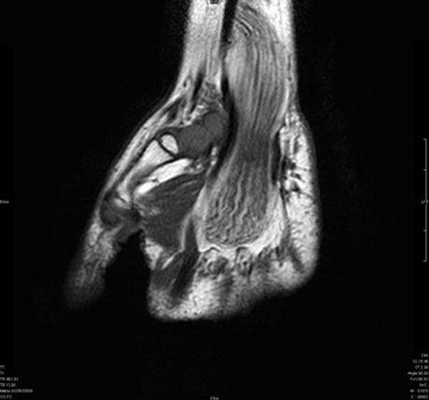

Клинически: Острая боль. В анамнезе нет травмы или чрезмерной нагрузки. Увеличение диаметра и повышение МР-сигнала в проекции сухожилия разгибателя.

Кистозное образование в проекции тыльных межзапястной и лучезапястной связок; незначительный синовит.

Синдром повреждения сухожилий

Синдром повреждения сухожилий включают частичные и полные их разрывы, проявления теносиновита и посттравматического тендиноза. Основную долю составляют теносиновиты, возникающие изолированно или на фоне повреждения костей и связок. Морфологически теносиновиты характеризуются скоплением синовиальной жидкости под оболочками сухожилия. Рентгенодиагностика в диагностике теносиновитов неинформативна. Наиболее информативны в диагностике теносиновита УЗИ и МРТ.

Теносиновит сухожилий глубокого сгибателя пальцев кисти и длинного сгибателя большого пальца.